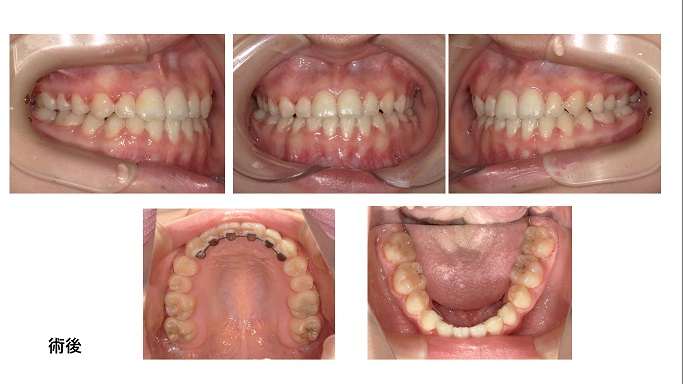

矯正症例74 骨格性下顎前突 カムフラージュ矯正

診断:骨格性下顎前突。性別;女。治療開始年齢、14歳3か月。動的治療終了年齢16歳9か月。来院回数:35回、治療費総額987,8000円(税込み)

抜歯部位:下顎左右4番、マルチブラケット法によるカムフラージュ矯正

骨格性下顎前突のカムフラージュ矯正です。今回はエッジワイズブラケットを使用しました。(骨格性下顎前突の場合KBTマルチブラケットシステムを使う場合が多い)その場合の治療のポイントは骨格的不調和を歯列弓で折り合い付けるために、ワイヤーのサイズダウンです。